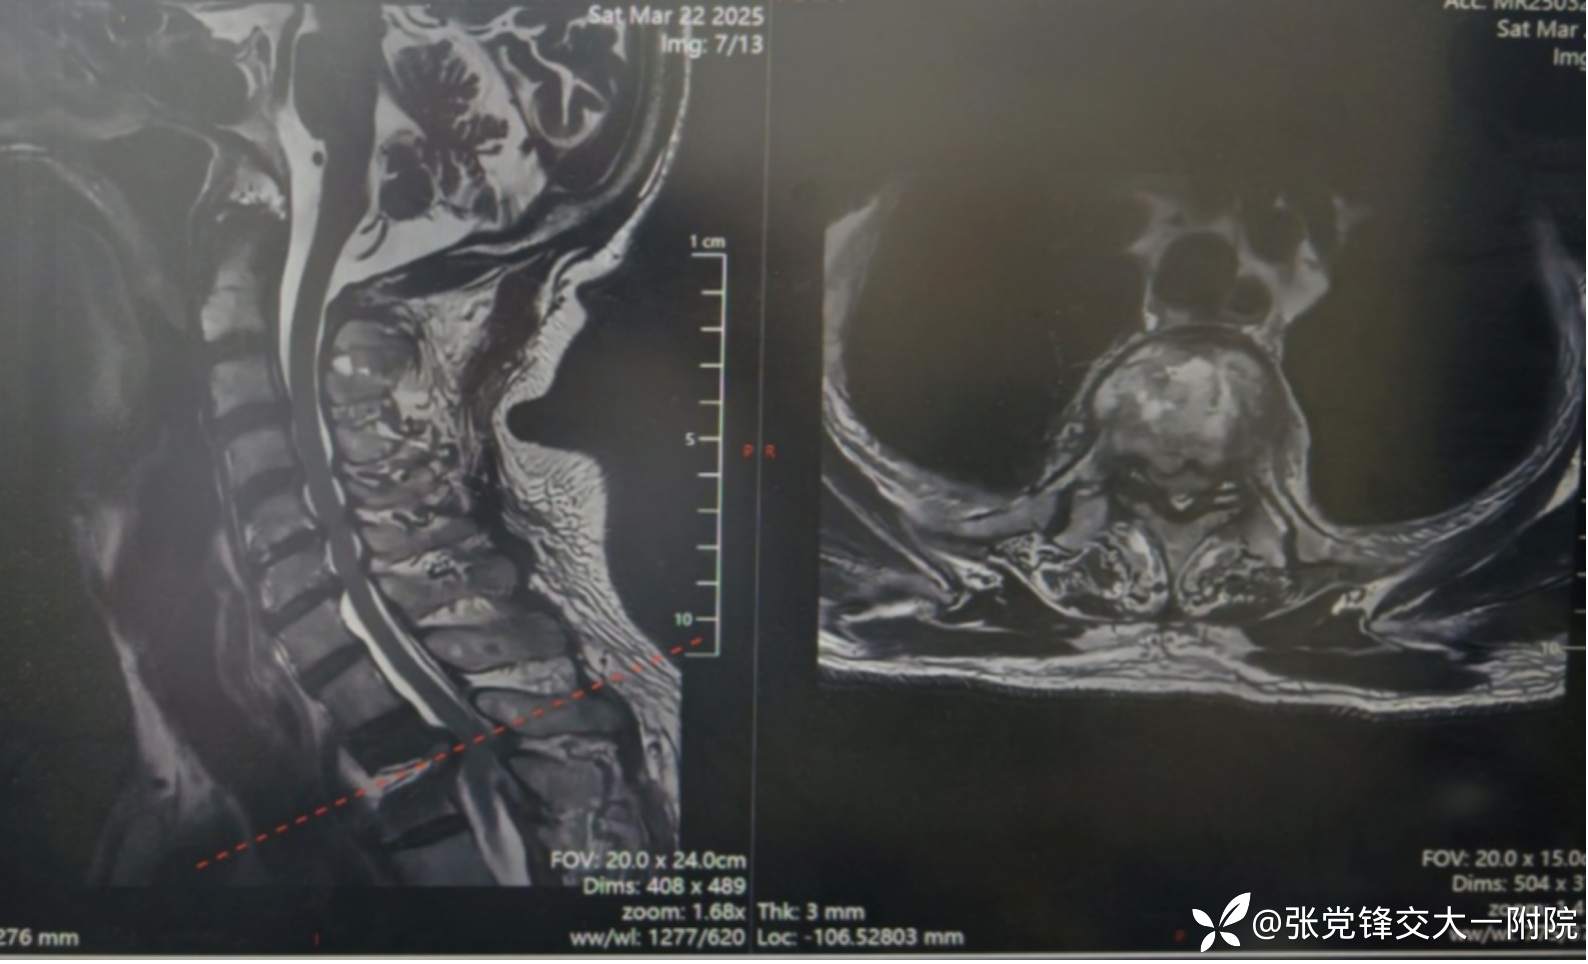

【影像学检查】

术前MRI

全身骨显像:胸2-3椎体骨代谢增高,结合病史考虑脊柱结核可能。